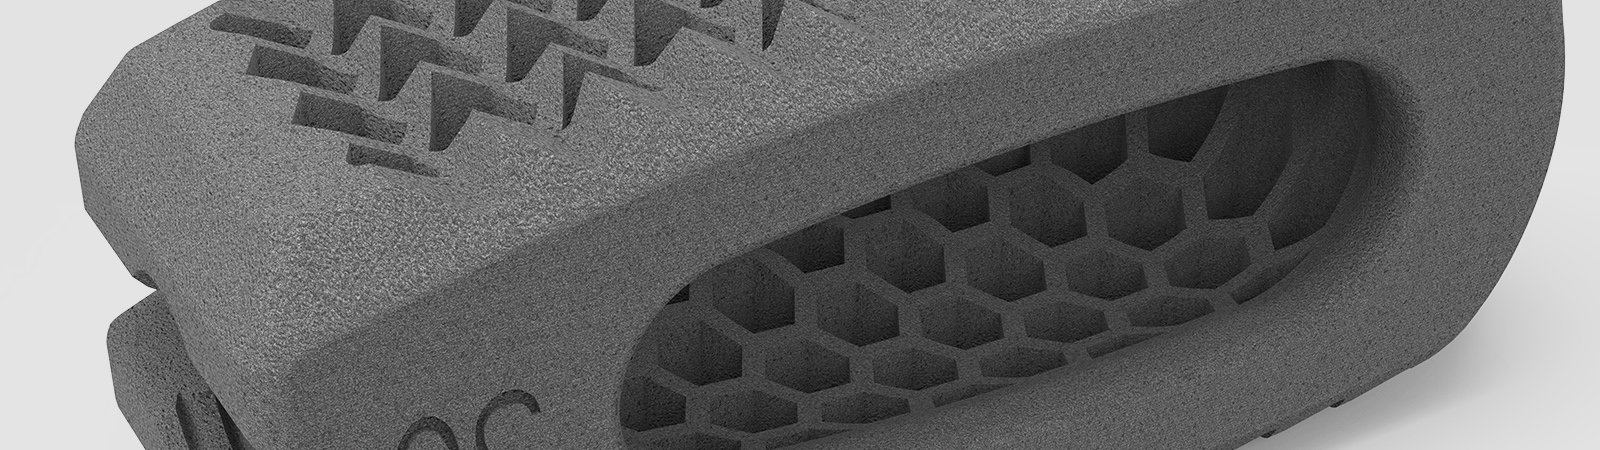

zurückLOCC-SLMPLIF aus Titan

LOCC bedeutet »Lateral Offset Contact Cage«. Der Name steht für eine optimal laterale Abstützung. Durch sein kurviertes Design am lateralen Anteil wird eine zusätzliche Abstützung am äußeren Rand des Wirbelkörpers generiert. Die Last wird somit auf den gesamten Wirbelkörper sicher verteilt.

zurückUNI-LOCC-SLMOblique-Cage aus Titan

Uni-LOCC bedeutet »Unilateraler Offset Contact Cage«. Der Name steht durch seine spezielle Kurvierung für eine optimale laterale Abstützung. Verlängert um einige Millimeter, wird die Last beim schrägen Einbringen auf den gesamten Wirbelkörper optimale verteilt.

zurückMOONY-SLMTLIF aus Titan

MOONY bietet durch seinen schwenkbaren Universaleinbringer ein sicheres und einfaches Einbringen des Cages. Das patronenförmiges Design, sowie Finnen auf der Grund und Deckplatte des Implantates, lassen den Cage sehr elegant in den interkorporellen Bereich gleiten.

zurückLAMBDA-SLMALIF aus Titan

LAMBDA ist ein Cage mit einem speziellen Oberflächendesign. Die Oberfläche ist so gestaltet, dass Grund- und Deckplatten beim Einbringen des Cages angefrischt werden, um so eine optimale Kapilarisierung des interkorporellen Bereiches zu generieren.